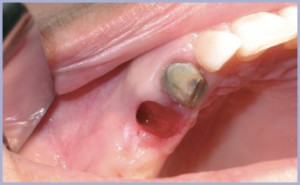

Si procede quindi all’inserimento di un impianto post-estrattivo in regione 1.4 (figg. 2-4).

- Fig. 2